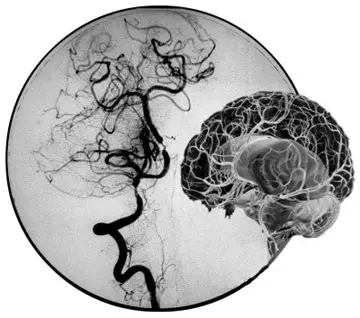

DSA图片上提示颅底血管烟雾现象

“烟雾病”,原本是起源于日本的一类疾病,又称“Moyamoya病”或“脑底异常血管网症”,是一组以颈内动脉虹吸段及大脑前、中动脉起始部狭窄或闭塞,脑底出现异常的小血管网为特点的脑血管病。因脑血管造影时呈现许多密集成堆的小血管影,似吸烟时吐出的烟雾,故名烟雾病。

目前明确的病因明确,跟遗传有关,可能有与后天血管的变态炎症反应有关。主要临床症状有表现为“缺血性脑卒中”和“出血性脑卒中”的临床症状,还可表现为癫痫发作。病程发作复杂多变,可反复发作并发作规律不可预测,预后较差。诊断主要可通过头颅MRA(注:磁共振血管造影)或CTA(注:CT血管造影)确诊,最能明确诊断是脑血管DSA(注:Digital Subtraction Angiography,血管造影)检查,发现颈内动脉末端及大脑前、中动脉起始端狭窄或闭塞,并见颅底出现明显异常的小血管网。可通过手术或内科的药物治疗,但效果欠佳,易反复发作。

提到烟雾病这个新鲜的词汇,很多人可能要和抽烟连在一起,其实两者根本就不相关。“之所以叫烟雾病,其实是一个形象描述大脑像烟雾状的小血管的特征。”暨南大学附属第一医院神经外科王向宇主任告诉记者,发生烟雾病时,脑内主要血管会因各种不明确原因(如遗传、感染、血管炎、青少年动脉粥样硬化、放射治疗等)变得狭窄甚至阻塞,导致脑缺血。这时大脑为了拯救因缺血而逐渐枯萎的神经元,就会从已经变狭窄的大血管上生出小血管来缓解缺血状况,这些小血管交叉成网状,一旦做数字剪影血管造影检查,医生就会发现像吸烟时喷出的烟雾状血管网,为此称为“烟雾病”。